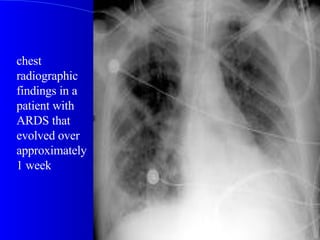

chest radiographic findings in a patient with ARDS that evolved over approximately 1 week

chest radiographic findingsin a patient with ARDS that evolved over approximately 1 week